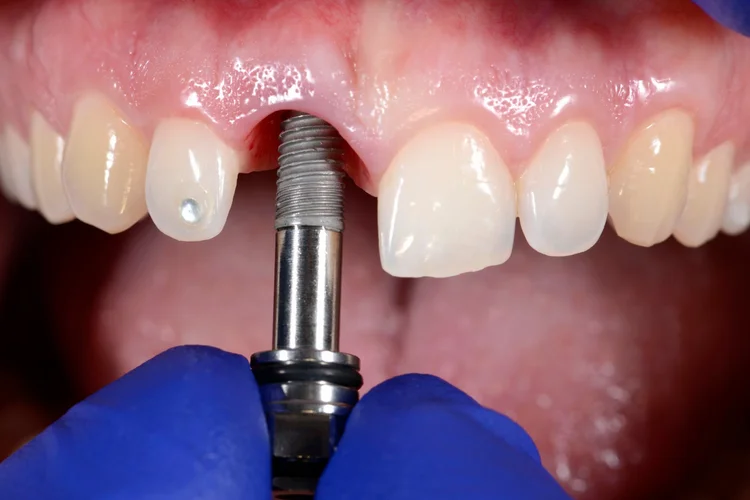

Nous concevons et fabriquons des couronnes, des bridges et des gouttières à l'aide des dernières imprimantes 3D et fraiseuses disponibles dans nos locaux. Cela garantit une qualité optimale, un ajustement parfait et un délai d'exécution court.

Pour ce faire, nous réalisons des radiographies (si nécessaire), des photos couleur et toujours des modèles numériques 3D de votre dentition. Nous examinons vos dents, vos gencives et vos muqueuses afin de détecter à temps toute anomalie ou maladie. Nous vérifions également la couleur et la position de vos dents.